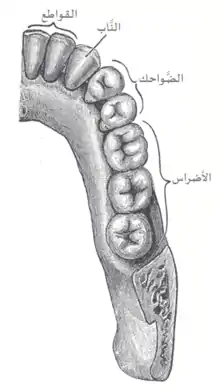

أنواع الأسنان

تأخذ الأسنان عند الإنسان (كما باقي الثدييات) الأشكال الآتية:

- القواطع: ثنايا، ورباعية

- الأنياب

- الضواحك أو النواجذ

- الأضراس (كما تعرف بالأرحاء أو الطواحن)